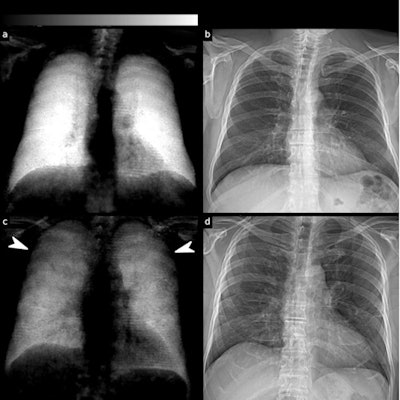

(a) Dark-field and (b) conventional (attenuation-based) chest radiographs of a healthy subject. The dark-field radiograph exhibits a strong, homogeneous dark-field signal. The respective attenuation-based image shows no apparent pathology. (c) Dark-field and (d) attenuation-based chest radiographs of a patient infected with COVID-19. Compared with the healthy subject, the infected patient shows an overall decrease of signal intensity. While the signal of the healthy subject is homogeneous, the dark-field signal of the infected patient appears inhomogeneous and patchy, especially in the periphery of the lung (arrowheads). Image courtesy of Research Square.

(a) Dark-field and (b) conventional (attenuation-based) chest radiographs of a healthy subject. The dark-field radiograph exhibits a strong, homogeneous dark-field signal. The respective attenuation-based image shows no apparent pathology. (c) Dark-field and (d) attenuation-based chest radiographs of a patient infected with COVID-19. Compared with the healthy subject, the infected patient shows an overall decrease of signal intensity. While the signal of the healthy subject is homogeneous, the dark-field signal of the infected patient appears inhomogeneous and patchy, especially in the periphery of the lung (arrowheads). Image courtesy of Research Square.In a receiver operating characteristic (ROC) analysis for the differentiation between infected patients and healthy subjects, the effect size expressed as area under the ROC curve (AUC) was 0.78 for standard radiographs, 0.91 for dark-field images, and 0.93 for the combination of both.